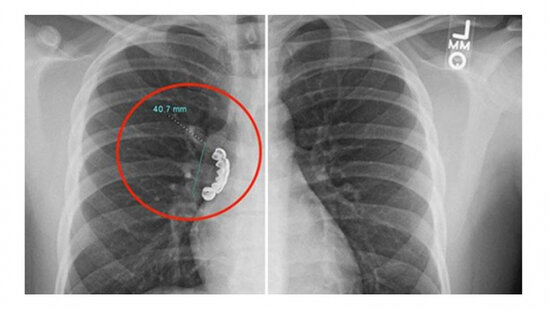

22 yaşlı gəncin protez dişi ağ ciyərinə batdı - FOTO

Amerika Birləşmiş Ştatlarında 22 yaşlı gəncin taxma dişi ciyərinə batıb.

BAKU.WS xarici KİV-ə istinadən xəbər verir ki, Uiskonsin əyalətində yaşayan gənc epilepsiya (beyindəki neyronların anidən və nəzarətsiz şəkildə boşalması) keçirən zaman gümüşdən olan pratezini udub.

Bundan sonra o, şiddətli öskürək və ciyərlərində xışıltı olaması səbəbilə həkimə aparılıb. Orqanları rentgenə salınan zaman ağ ciyərində 4 sm uzunluğunda taxma diş aşkar edilib.

Həkimlər gəncin ağ ciyərindəki protezi çıxarıblar. Müalicələr aparıldıqdan sonra isə o, xəstəxanadan evə buraxılıb.